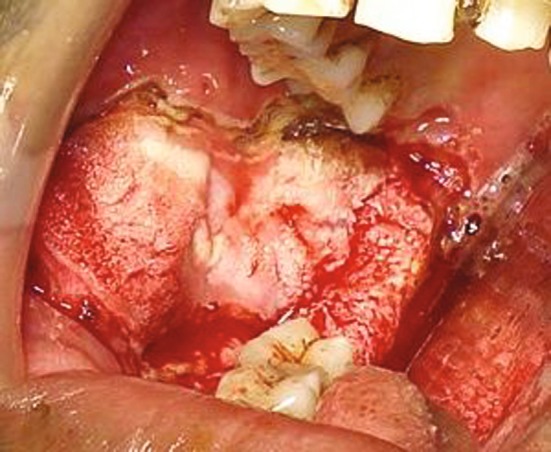

Fig. 2.

Lesion at the time of surgery, verrucous changes seen at the intermediate zone connecting the two areas as seen pre-operatively